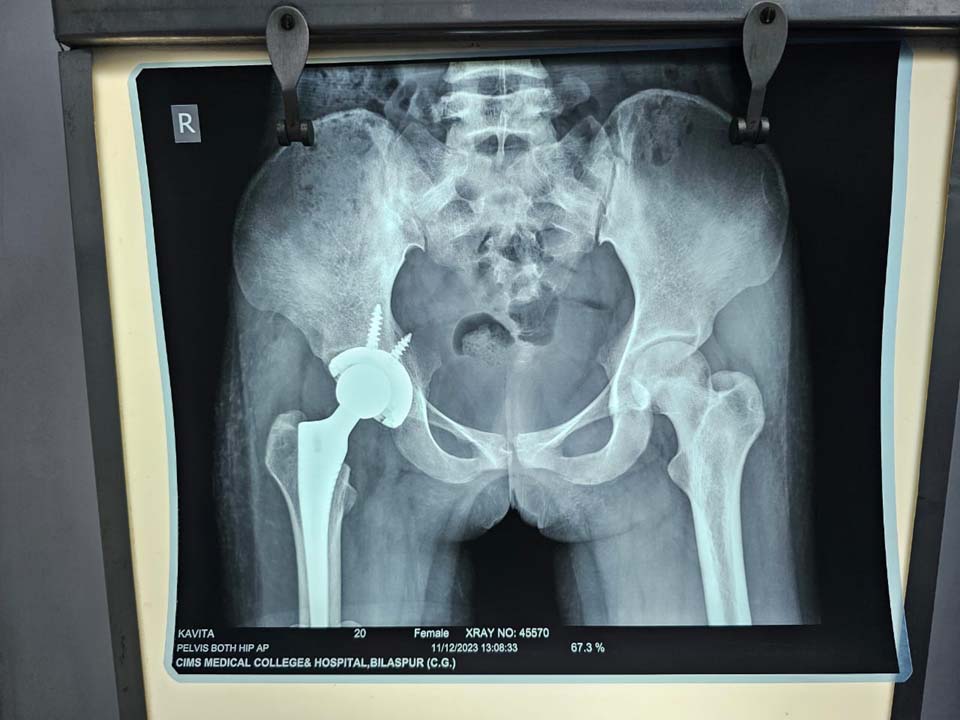

बिलासपुर 18 जनवरी 2024। पामगढ़ ब्लॉक के एक गरीब किसान की बेटी का सिम्स अस्पताल में सफल टोटल हिप रिप्लेसमेंट सर्जरी किया गया है। प्रधानमंत्री जन आरोग्य योजना से लगभग ढाई लाख रुपए की सर्जरी के लिए उसे एक भी पैसा देना नहीं पड़ा। निजी अस्पतालों में जांच और इलाज का खर्च सुनकर वे निराश हो गए थे। सिम्स अस्पताल प्रबंधन ने गरीब और हताश मरीज का हौसला बढ़ाया और सही मार्गदर्शन के साथ सफल इलाज कर उनका दिल जीत लिया है।

सिम्स अस्पताल के उप अधीक्षक डॉ विवेक शर्मा ने बताया की डॉक्टरों ने 21 वर्षीय सिक्स सेल से ग्रसित गंभीर मरीज जो कि विगत 2 वर्ष से अपने दाएं कूल्हे के दर्द से परेशान थी। उसे चलने फिरने एवं उठने बैठने में भी दिक्कत हो रही थी । यहां तक कि दैनिक प्रसाधन में भी परेशानी हो रही थी। बहुत से डॉक्टर को दिखाने के बाद भी उसे सही इलाज नहीं मिल रहा था । बिलासपुर में प्राइवेट अस्पतालों में दिखाने के बाद उसे कुल्हा बदलने की सर्जरी जिसे टोटल हिप रिप्लेसमेंट सर्जरी कहा जाता है, की सलाह दी गई, जिसका खर्चा खर्चा दो से ढाई लाख रुपए बताया गया ।चूंकि मरीज के पिता गरीब किसान हैं, इसलिए यह खर्च उठाने में सक्षम नहीं थे। मरीज को उनके परिजनों ने बताया कि यह ऑपरेशन सिम्स में भी होता है, जिसकी वजह से मरीज के पिता सिम्स के अस्थि विभाग के एसोसिएट प्रोफेसर डॉ राजीव सखूजा से इसकी सलाह ली ।

डॉ राजीव सखूजा ने मरीज की पूर्ण जांच कराई, जिसमें उन्होंने यह पाया कि मरीज की 75 प्रतिशत रक्त कोशिकाएं सिकल सेल से प्रभावित हैं, जो कि अपने आप में एक बहुत बड़ा रिस्क है। सिकल सेल की वजह से उसके कूल्हे की हड्डियां पूरी तरह खराब हो चुकी हैं। मरीज के पिता अपनी बेटी के असहनीय वेदना को देखते हुए यह जोखिम उठाने को भी तैयार हो गए। इसके बाद मरीज का पूर्ण रूप से निश्चेतना एवं मेडिकल फिटनेस परीक्षण कराया गया । जिसके बाद मरीज का टोटल हिप रिप्लेसमेंट का सफल ऑपरेशन डॉ राजीव सखूजा एवं उनकी टीम ने किया। मरीज अब पूर्णत स्वस्थ है । कोई दर्द नहीं है एवं बिना सहारे के चल पा रही है । यह ऑपरेशन पूर्ण रूप से प्रधानमंत्री जन आरोग्य योजना के अंतर्गत निशुल्क किया गया है। उनके पिता ने संपूर्ण अस्थि रोग विभाग, निश्चेतना विभाग, एवं मेडिसिन विभाग को बधाई दी । इस ऑपरेशन में डॉ ए आर बेन, डॉक्टर तरुण सिंह ठाकुर डॉ सागर केसरवानी एवं डॉ दीपक शामिल थे। निश्चेतना विभाग से डॉक्टर राकेश निगम डॉक्टर भावना रायजादा डॉक्टर मिल्टन देव वर्मा एवं उनकी टीम का सहयोग रहा। नर्सिंग टीम में सिस्टर सरिता बहादुर, सिस्टर योगेश्वरी, सिस्टर दीप्ति, सिस्टर मीना, सिस्टर रितु तथा छन्नू , गिरीश, संतोष एवं देव का योगदान रहा। सिम्स के अधिष्ठाता डॉक्टर के के सहारे ने सभी डॉक्टरों की सराहना की।